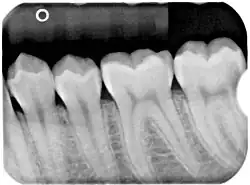

Panoramic(figure 1) and apical(figure 2) radiographs are commonly utilised in routine examinations to aid in the initial detection of BBC.[15] BBC is characterised by a well-defined radiolucent lesion on the buccal aspect of the tooth extending from furcation to the root apices.[19][20] With the presence of periosteal reaction on the buccal aspect of the tooth.[21][22] Tilting of the affected molars, with the apices of the roots tilted lingually and cusp tip buccally.[21][22] Unlike a periapical cyst, the periodontal ligament space and lamina dura remain intact and continuous, suggesting that the lesion is not directly associated with the root apices.[15][21][22]

Panoramic and periapical X-rays are usually performed first to identify the radiolucency on the buccal aspect of the tooth of interest, without involving the apex of the tooth.[13] The roots of the impacted tooth are usually bound by a well-defined radiolucent lesion.[13]